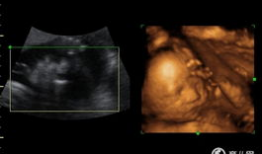

四维视频,四维视频揭秘未知世界

哇,你有没有想过,未来看电影会是什么样子?想象你戴上眼镜,眼前不再是平面的画面,而是一个立体的世界,仿佛你真的置身其中。这就是四...